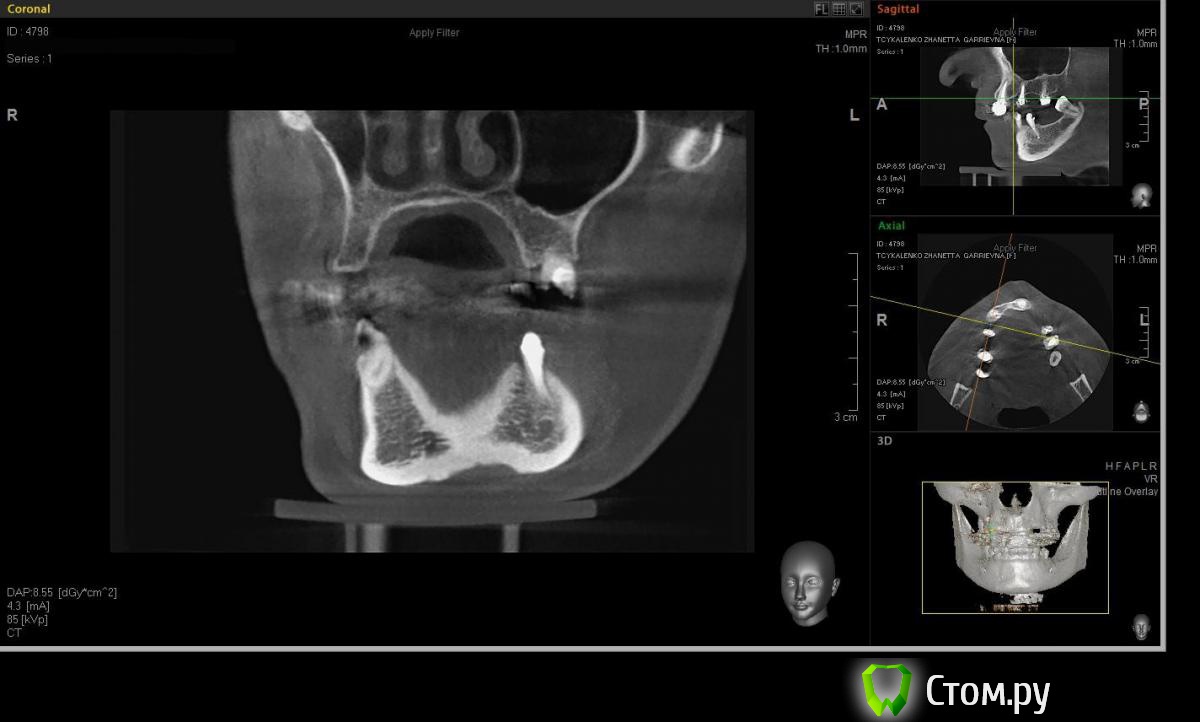

Евгений Ходыкин Опубликовано 20 мая, 2014 Поделиться Опубликовано 20 мая, 2014 Коллеги, прошу помощи в определении варианта аугментации в области 1.4 для адекватной в протетическом плане постановки имплантата. Адекватно ли здесь будет расщепление гребня при той оси импланта, которую я схематично выставил? Всем заранее спасибо) Ссылка на комментарий

Евгений Ходыкин Опубликовано 20 мая, 2014 Автор Поделиться Опубликовано 20 мая, 2014 Замерил... Ссылка на комментарий

АнтонТЛТ Опубликовано 20 мая, 2014 Поделиться Опубликовано 20 мая, 2014 А теперь замерьте угол в районе 15 зуба через фиссуру Ссылка на комментарий

Евгений Ходыкин Опубликовано 20 мая, 2014 Автор Поделиться Опубликовано 20 мая, 2014 Ну как-то так. Сути не уловил) Свой зуб стоит совсем иначе, да и ширина гребня иная совсем... Ссылка на комментарий

АнтонТЛТ Опубликовано 20 мая, 2014 Поделиться Опубликовано 20 мая, 2014 Суть в том, что изначально не правильно угол замерили 1 Ссылка на комментарий

Евгений Ходыкин Опубликовано 20 мая, 2014 Автор Поделиться Опубликовано 20 мая, 2014 Суть в том, что изначально не правильно угол замерилиДак изначально я замерил строго по гребню, в условиях наибольшей ширины гребня, там угол под 30 и выходил. При ангуляции как у 1.5 у меня и получается дефицит кости, что примерно изобразил на схеме постановки имплантата. Поправьте, если не прав... Ссылка на комментарий